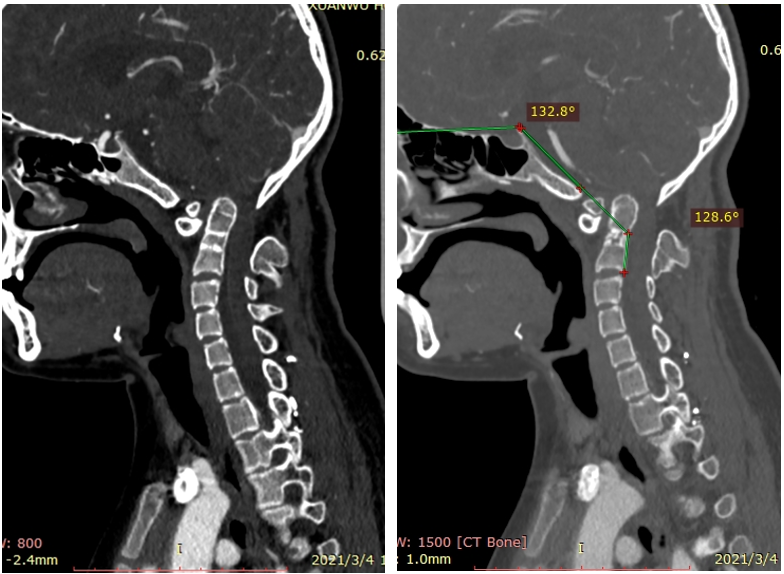

女,13岁,154cm,57kg

• 6个月前病人出现颈部活动受限,3个月前出现左手力弱

影像资料:

• 齿状突小体

• 寰枢椎脱位